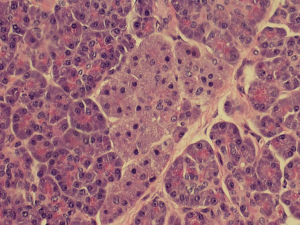

Histopathological analysis of the specimen revealed complete excision of the mass, which was reported to be benign pancreatic tissue, showing both endocrine and exocrine elements (islets of Langerhans, pancreatic acini, and pancreatic ducts) (Figures 4-9). No atypical features were seen and there was no evidence of malignancy.

The histological morphology of EP tissue can be classified according to Heinrich’s criteria, proposed in 1909 (9). Type 1 EP tissue contains cells of exocrine glands, excretory ducts and islets of Langerhans; type 2 contains only excretory glands and excretory ducts; type 3 contains only excretory ducts (8). In 1973, Gasper-Fuentes proposed a modified version of the Heinrich criteria, comprising of four types of EP tissue:

- Type I: typical pancreatic tissue composed of acini, ducts and islet cells;

The patient reported herein is classified under type I.